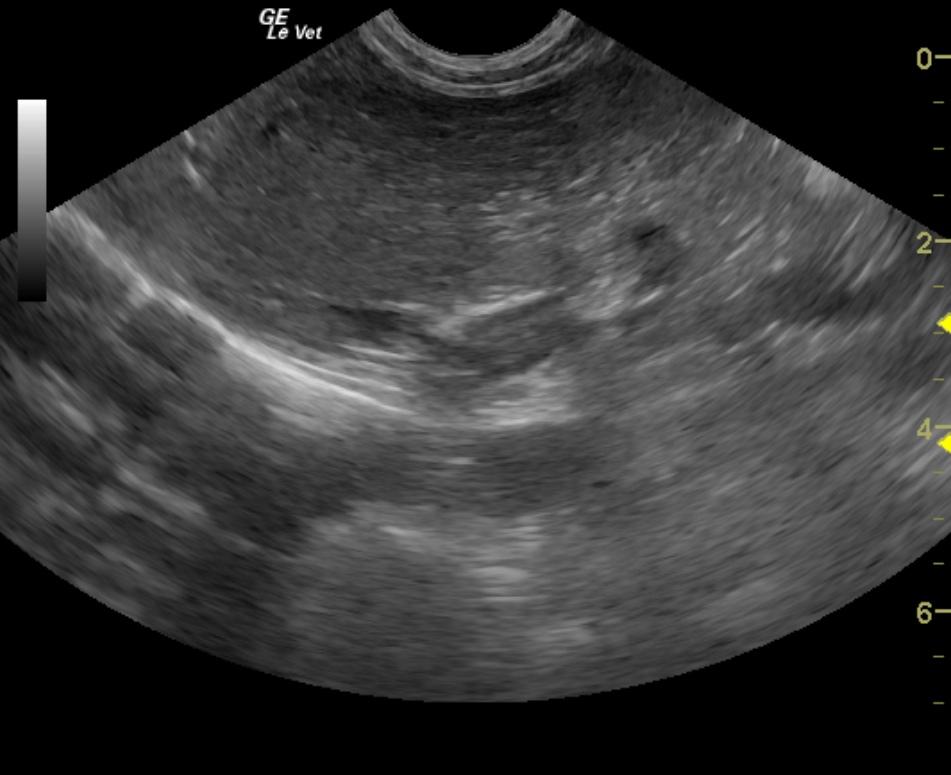

An 11-year-old FS dog was evaluated and presented for alopecia, panting, excessive water drinking, and polyphagia. Urinalysis and CBC were both within normal limits. Abnormalities on blood chemistry were hyperproteinemia, hyperphosphatemia, elevated GGT activity, elevated BUN:creatinine ratio, and hypercalcemia. An ACTH stimulation test was suggestive of hyperadrenocorticism.